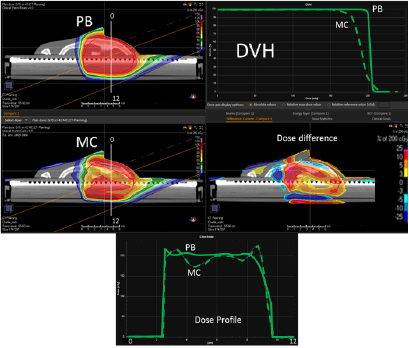

In figure 4, on the top we have the PB dose distribution optimized with our TPS that showed a good uniformity and conformity to the target of the 1/6 head phantom for a proton field angle of 70° and snout position 42 cm from the isocenter. The MC recalculation of the experimental setup (oblique field and superficial target on the anthropomorphic phantom) showed significant differences with respect to the PB calculation, with under-dosage up to 25% in the target and over-dosage up to 30% outside the target.

Figure 4. PB optimized dose distribution on the 1/6 head phantom (top left) and the MC recalculation (middle left) with a proton field angle of 70° and the RS 42 cm from the isocenter (i.e. air gap ~24 cm). The white lines represent the dose profiles' (bottom) extraction plans. On the right side of the figure, the DVHs of both the dose distributions (top right) and dose difference (middle right) are displayed.

Standard image High-resolution imageThe MatriXX measurement of the configuration represented in figure 4, confirmed what was expected from the MC recalculation: the PB dose profile was higher compared to the measurements and the γ passing rate of the dose distribution estimated on the MatriXX was 57.6%. The MC recalculation is much closer to the experimental data and had a gamma passing rate of 97.8% (see figure 5 and table 1).

Figure 6 reports the PB dose distribution of a plan optimized on the two slabs of the head phantom and its MC recalculation.

Figure 6. PB optimized dose distribution on the 2/6 head phantom (top left) and MC recalculation (middle left) with a proton field angle of 70° and the RS 42 cm from the isocenter (i.e. air gap ~26 cm). The white lines represent the dose profiles' (bottom) extraction plans. On the right side of the figure, the DVHs of both the dose distributions (top right) and dose difference (middle right) are displayed.

Standard image High-resolution imageThe dose differences between the PB and MC are less pronounced for this configuration compared to the previous one (figure 7 and table 2). Again, it is worth noting that the MatriXX plane of measurement was not placed in the region where the largest disagreement occurs (figure 6).